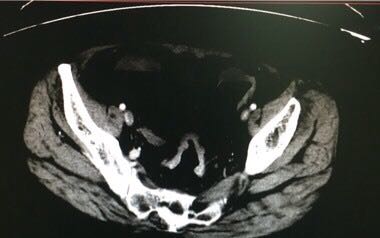

60岁女性,便血2月入院,肠镜发现距肛门6厘米隆起型肿物,活检为腺癌,完善术前检查,发现肝右叶下极低密度肿物,边界不清,怀疑为肝转移。同期切除可行吗?